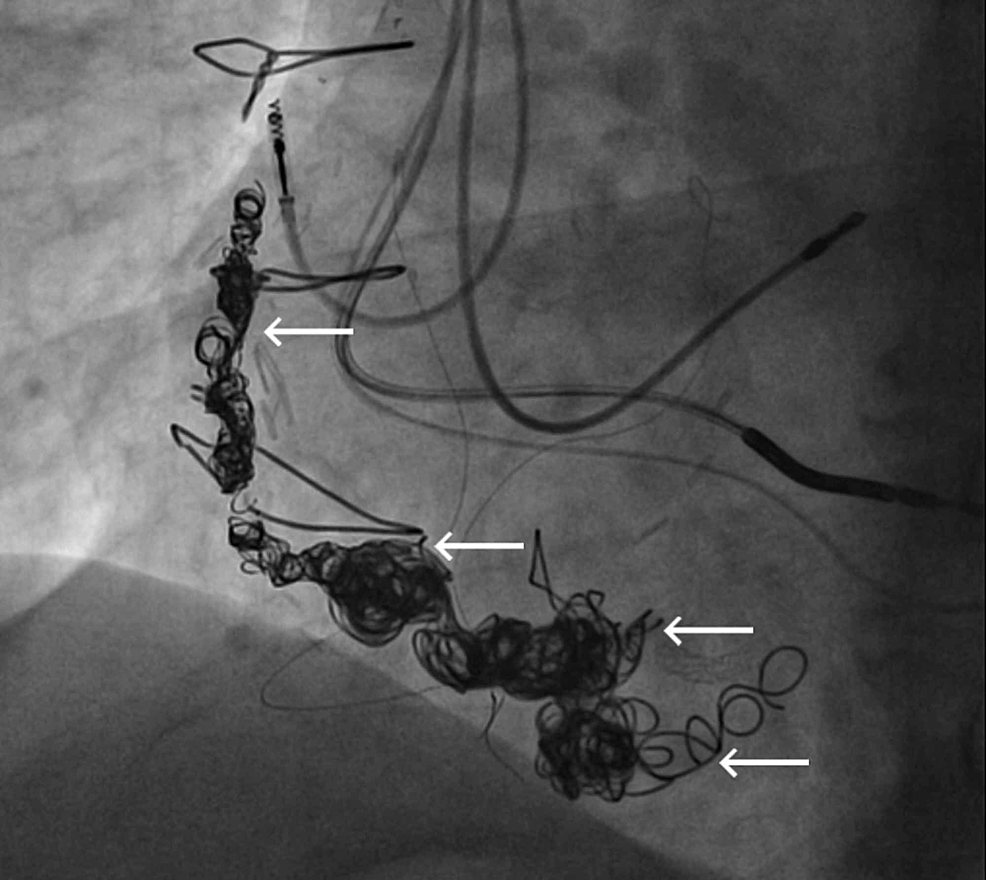

Features of SVG venous graft aneurysm

- Vascular plug

- Multiple coils (Does coil occlusion offer a permanent cure? I can’t think so )

- Covered stent